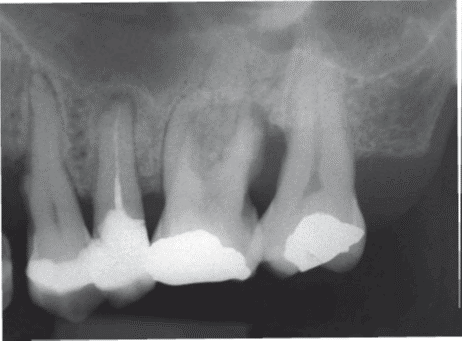

La tomografía computarizada cone beam (TCCB) ha adquirido una importancia creciente en periodoncia debido a su capacidad para proporcionar imágenes tridimensionales de las estructuras dentales y periodontales. A diferencia de las radiografías convencionales, que ofrecen únicamente una representación bidimensional, la TCCB permite una visualización más detallada de la anatomía ósea y de las estructuras que...

Errores de posicionamiento de implantes dentales en relación con estructuras anatómicas en el maxilar superior

Los implantes dentales constituyen una alternativa eficaz para la rehabilitación bucodental y contribuyen a la calidad de vida de los pacientes. No obstante, el procedimiento de colocación de implantes no está exento de errores técnicos, que pueden producirse como consecuencia de fallos en la planificación quirúrgica o en la identificación precisa de las estructuras anatómicas....